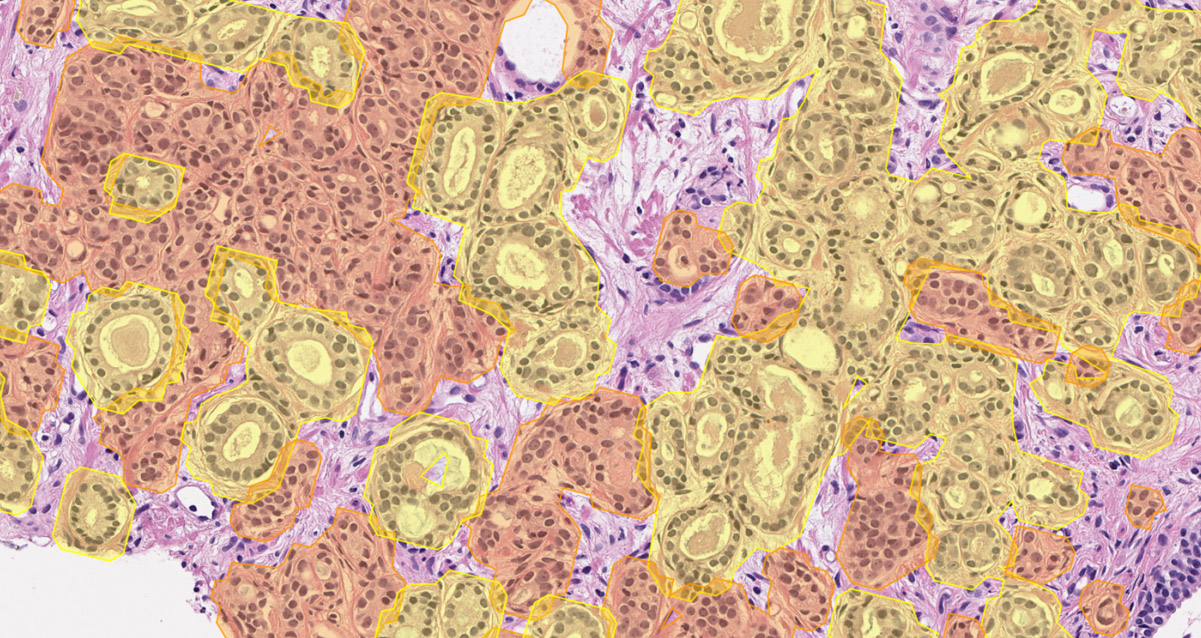

DeepDx® Prostate identifies cancer severity, coloring tissue regions based on Gleason pattern classification results, and suggests Gleason scores and grade group.

The solution highlights the cancerous lesions of the Gleason pattern 3, 4, and 5 and generates 3 different colored overlays on the slide images.

The proportions of each Gleason pattern out of the total tumor area and tumor-to-tissue ratios are automatically quantified.